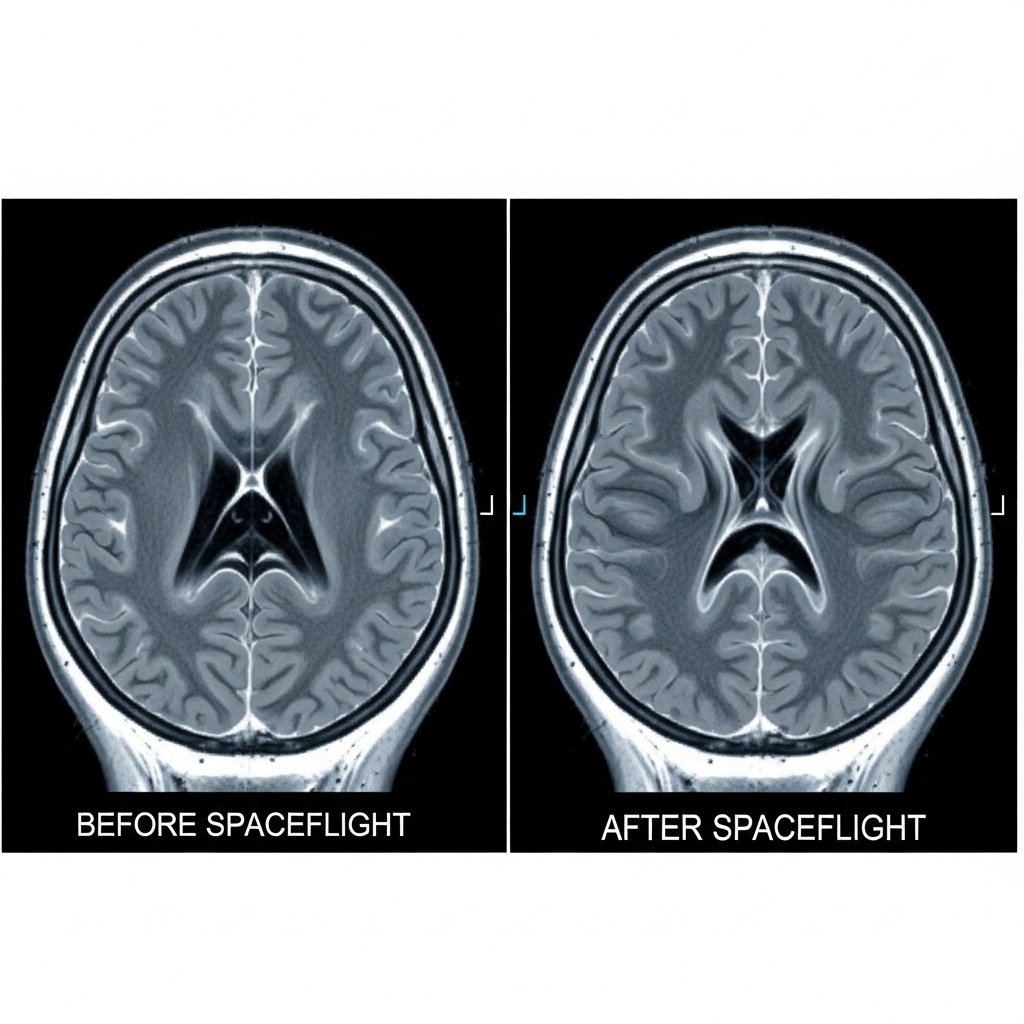

Brain imaging shows upward displacement of brain tissue following extended missions. Cerebrospinal fluid movement changes under microgravity, placing pressure on upper regions. Researchers observed measurable elevation near the top of the skull. Such movement links directly to fluid redistribution rather than injury or disease.

The cerebrospinal fluid is contained in the ventricles and the pressures are regulated. Months after being in orbit, the size of ventricular spaces increases. MRI of astronauts demonstrates the continued enlargement of MRI weeks post-return. Growth implies reduced drainage of the fluid in microgravity, which develops pressure variations within the skull.

Here on earth, gravity helps in the flow of fluids on the lower body. Fluids move towards the head in orbit. This change changes the circulation of cerebrospinal fluid. Fluid pooling is visualized as being more in the areas around the upper part of the brain and this is as expected through tissue migration patterns.